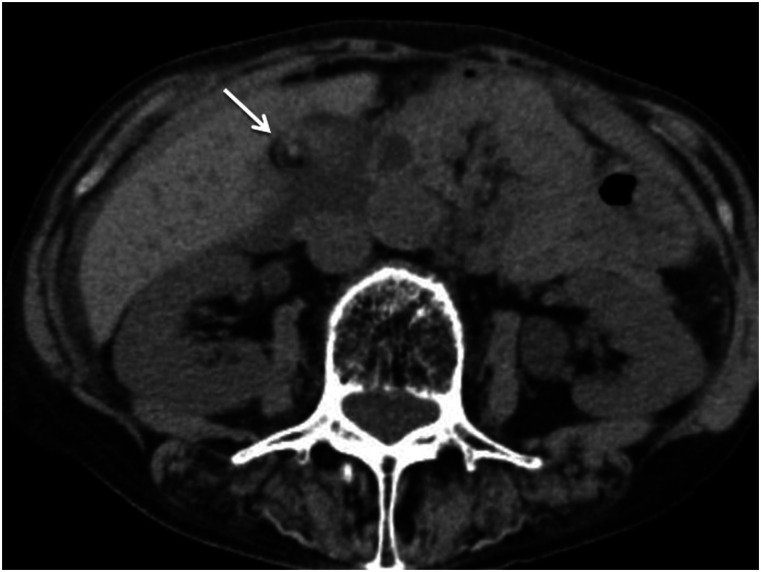

The purpose of this report was to evaluate the usefulness of hyperdense whirl sign on unenhanced computed tomography (CT) for diagnosing gallbladder torsion. The CT scans of seven patients with gallbladder torsion were independently reviewed by two board-certified radiologists for locating the high-density core with twisting between the gallbladder neck and liver bed, termed hyperdense whirl sign. The sign was observed in six cases. The detection of a hyperdense whirl sign on unenhanced CT appears useful for diagnosing gallbladder torsion.

Abstract Image